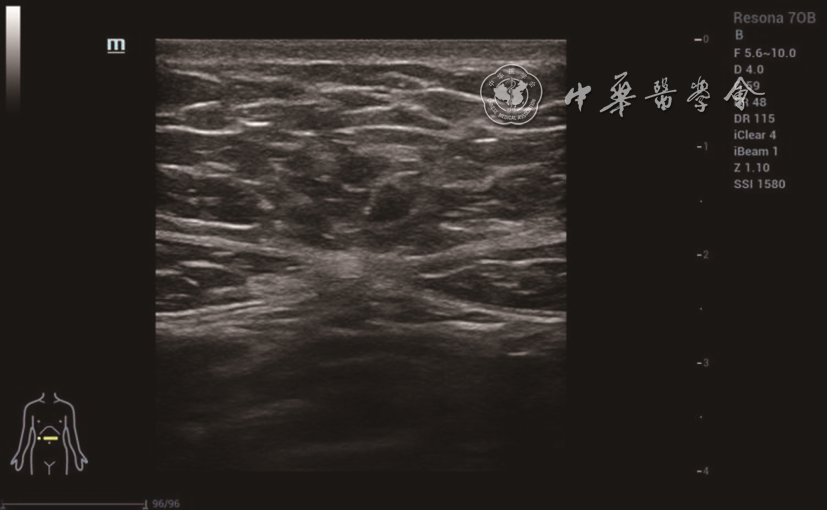

图1 22岁未育女性,脐上5 cm水平双侧腹直肌间距为0 cm